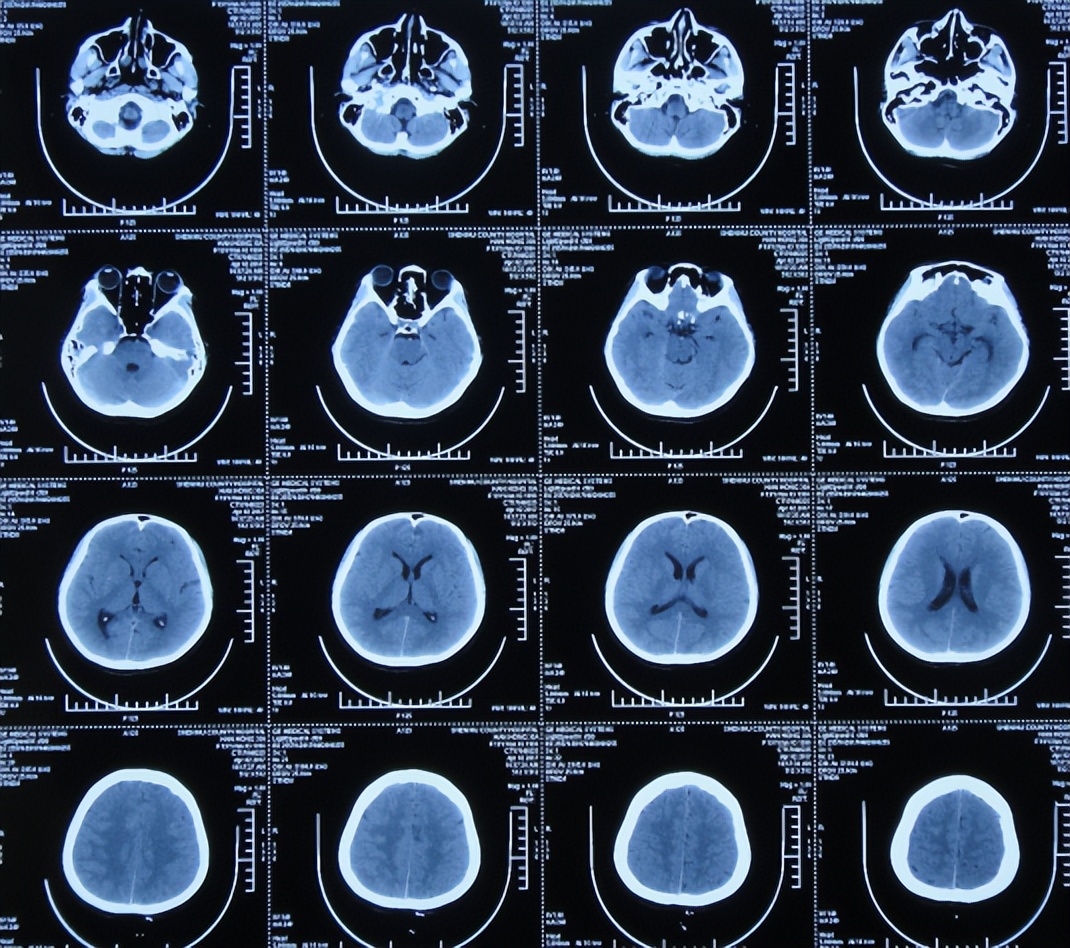

2017年4月2日(发病后13天),就诊于第2家的陕西省神木县某医院急诊外科,检查期间突发四肢软瘫、意识丧失、大小便*禁失**,查脑CT( 图-2 )后紧急收入ICU。

图-2: 2017年4月2日脑CT

行腰椎穿刺检查脑脊液常规:细胞高达1548×106 /L,淋巴细胞百分比56.8%,蛋白高达2266mg/l,糖1.15mmol/l,医院考虑结核性脑膜炎,家属当天晚上紧急将患者转至第3家的内蒙古的鄂尔多斯市某三甲医院。